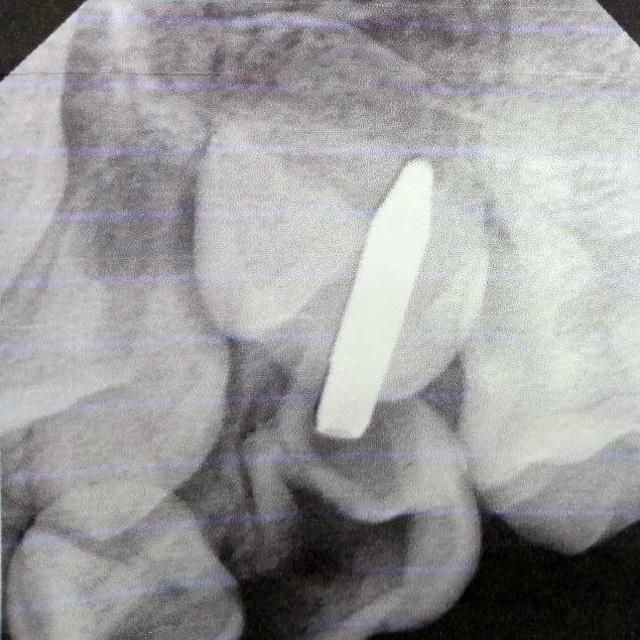

Ҫӗнӗ Шупашарта 8 ҫулти арҫын ача килте вылянӑ чухне ручкӑпа шӑлне чакаланӑ. Ӑнсӑртран вӑл ҫӗмӗрӗлсе кайнӑ, вӗҫӗ вара шӑлӗ ӑшӗнче юлнӑ.

Ача амӑшӗпе пӗрле стоматологи поликлиникине Алексей Аверьянов тухтӑр патне килнӗ. Пациента тӗрӗсленӗ, рентген тунӑ хыҫҫӑн пӗтӗмлетӳ тунӑ: шӑла кӑлармалла. Юрать-ха, вӑл сӗт шӑлӗ кӑна пулнӑ. Операци ӑнӑҫлӑ иртнӗ. Тухтӑрсем кайран тухмалли шӑл тымарне упраса хӑварнӑ.